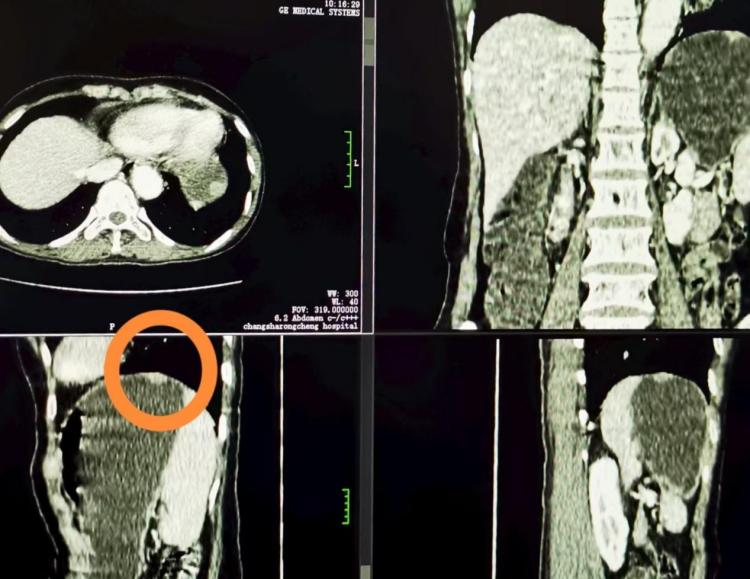

▲胃底肿瘤影像

胃部肿瘤的精准诊断是临床诊疗工作中的重点与难点。胃部低张(充水法)增强CT检查作为一项先进的影像诊断技术,能够更清晰地显示胃部黏膜病变、肿瘤浸润范围等,为疾病的早期发现、精准分期和治疗方案制定提供关键依据,提升胃壁肿瘤的检出率与诊断准确率。

在耐心讲解和细致示范下,融城医院放射科的医护人员快速掌握了该项技术的核心要点。随着设备的平稳运行,清晰的影像图像呈现在屏幕上,精准地显示出患者胃部的细微病变,首例胃部低张(充水法)增强CT检查宣告成功完成。